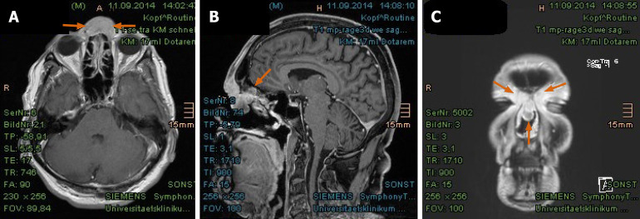

质子治疗前的检查显示,该患者鼻腔中央区域有显著强化信号,伴有鼻梁至鼻孔的软组织肿胀,测量大小约为29mm×15mm×22mm,紧邻额窦和颅底,左腮腺下极发现至少一个直径为8mm×11mm的明显强化结节。